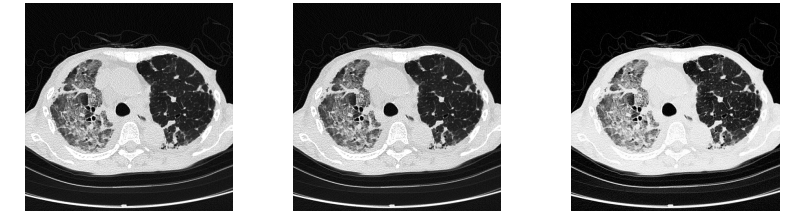

Poniżej zestawiono oceniane obrazy dla porównania:

1) Zgodność ze standardem DICOM część 14 przy odczycie badań monochromatycznych

Rys. 8 pokazuje, że dla 8,5 z 9 monochromatycznych obrazów (ok. 94%) tryb Hybrid Gamma PXL stosujący DICOM GSDF został oceniony na równi z trybem DICOM GSDF, a w jednym przypadku tryb Hybrid Gamma PXL stosujący DICOM GSDF oceniono lepiej niż tryb DICOM GSDF. Nie zdarzyło się natomiast, by tryb DICOM GSDF został oceniony lepiej niż tryb Hybrid Gamma PXL.

Jak wyjaśniono wcześniej, tryb Hybrid Gamma PXL stosuje DICOM GSDF dla wszystkich pikseli monochromatycznych. Wyniki testu potwierdziły, że obrazy monochromatyczne oglądane w trybie Hybrid Gamma PXL wyświetlają się prawidłowo.